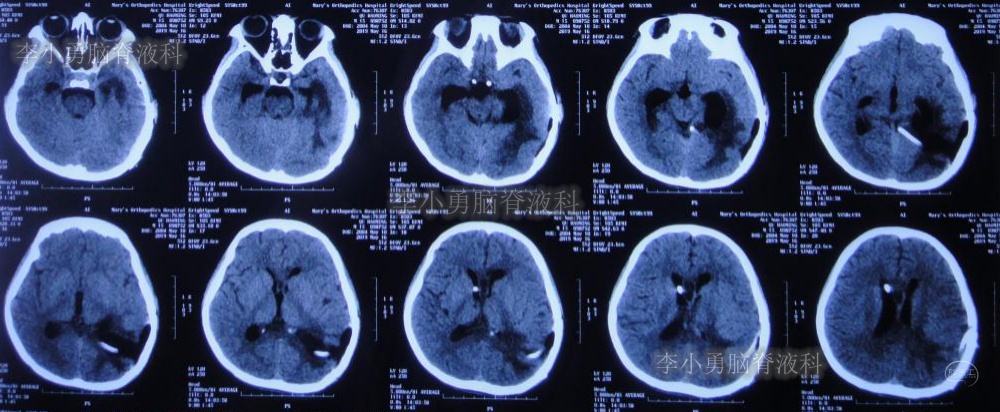

双侧脑室外引流5天后即2019年3月31日,脑脊液颜色由血性明显变淡,意识转清,肢体活动良好,给予复查头颅CT(图-3):脑室不大,残留少许积血。

图-3:2019年3月31日头颅CT:残留少许积血

双侧脑室外引流6天即2019年4月1日,给予常规拔除双侧脑室外引流管。但当晚再次出现剧烈头痛、烦躁及恶心,复查头颅CT(片子遗失)示脑室内再次出血,给予“对症处理”。

次日即2019年4月2日给予行腰椎穿刺术,引流出血性脑脊液;但腰椎穿刺术刚结束突然晕厥,再次复查头颅CT(图-4):脑室内出血量较前明显增多,四脑室及中央导水管铸形。

图-4:2019年4月2日头颅CT:脑室内积血明显增多